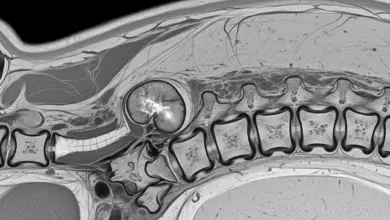

Escoliose é uma alteração tridimensional da coluna. Não é só “entortar” para o lado.

As vértebras também giram, o que muda o alinhamento do tronco e pode aparecer como assimetria de ombros, cintura ou costelas.

O risco mais discutido é o respiratório, pois curvas torácicas muito grandes podem reduzir a expansibilidade do tórax e diminuir a eficiência ventilatória.

Em escolioses muito graves, com ângulos altos e rotação importante, pode haver restrição pulmonar, cansaço aos esforços e piora progressiva da tolerância a atividades.

Em geral, quanto mais precoce a curva aparece e quanto mais ela progride durante o crescimento, maior o potencial de impacto no tórax.